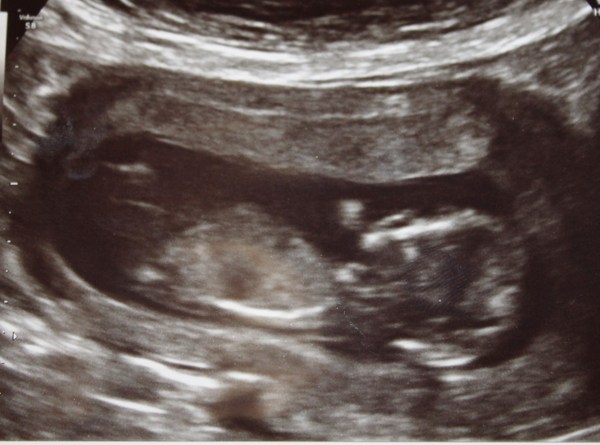

Fortunately, my head is full of lovely memories of tiny brain, tiny lungs, tiny beating heart, tiny spine, little legs, arms... etc. etc. etc. so far too happy to care right now about having blood test in 2 weeks instead.